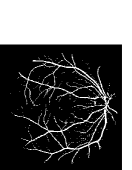

Figure 9: Ground truth (left) and segmentation result (right): (a) and (b) are the images from DRIVE dataset, (c) and (d) are the images from the STARE dataset

V-B Vessel Segmentation Performance

The segmentation performance of the proposed model on three public available datasets is given in Table IV. It can be observed that the proposed model can achieve more than 95%percent9595\% segmentation accuracy on the DRIVE, STARE and CHASE_DB1 datasets, with the highest accuracy score Acc=96.0%𝐴𝑐𝑐percent96.0Acc=96.0\% achieved in the DRIVE dataset. Some exemplary segmentation results are shown in Fig.9. When treating the unknown regions as background regions, AUC=0.833 of trimap is 2.6%percent2.62.6\% lower than the proposed model while Acc of trimap is similar to the proposed model. In addition, Se=0.679𝑆𝑒0.679Se=0.679 of trimap is 5.7%percent5.75.7\% lower than the proposed model. These observations show that trimap can already have good segmentation performance, which indicates that the selection of region features is very effective in segmenting blood vessels. From Table IV, it can be observed that the model with vessel skeleton extraction can achieve more than 5%percent55\% increase of Sensitivity𝑆𝑒𝑛𝑠𝑖𝑡𝑖𝑣𝑖𝑡𝑦Sensitivity and 2%percent22\% increase of AUC𝐴𝑈𝐶AUC compared with the model without vessel skeleton extraction while Acc𝐴𝑐𝑐Acc of the model with vessel skeleton extraction is similar to the model without vessel skeleton extraction, which demonstrates the effectiveness of vessel skeleton extraction.